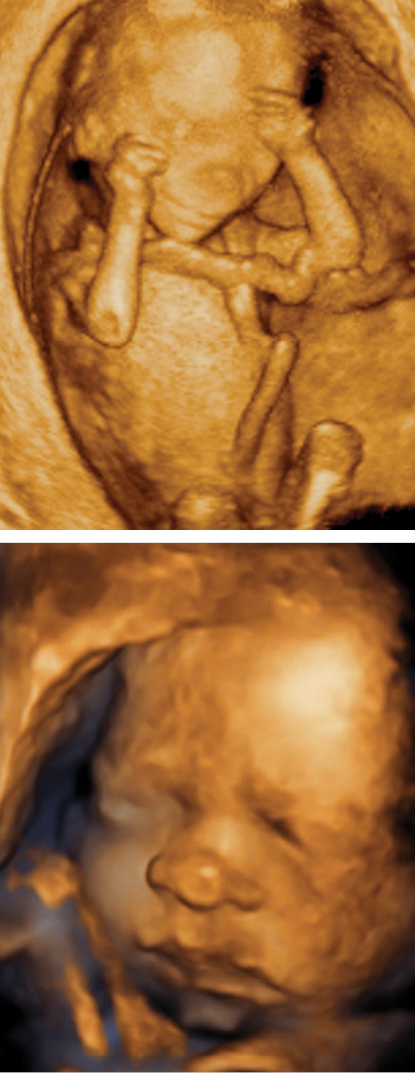

3D Obstetric Ultrasound Imaging Ultrasound imaging was first introduced in the 1950s and has since become the primary method of monitoring fetal development during pregnancy. 3D ... Fetch Content

3D fetal ultrasound - amazing things fetuses do in the womb - Dr. I. Shapiro - Duration: 8:37. israel shapiro 1,082,975 views. 8:37 3D ultrasound 25 weeks, 4D view of baby, 25 week pregnancy, baby girl, first view - Duration: 14:46. Elena ... View Video

Diagnostic Evaluation of the Fetal Face Using 3-Dimensional Ultrasound tal face with 3D ultrasound (3DUS) as well as 2-dimensional (2D) ultrasound. Rendered images allow the face to be dis-played as a curved structure, whereas multiplanar image dis- ... Access Full Source

3D/4D Ultrasound Imaging - Ultrasonic Industry Association